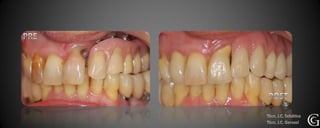

Prótesis Fija Convencional

Restauraciones periféricas totales “coronas”

Las coronas son restauraciones que involucran la totalidad del

diente, confeccionadas fuera de la boca (indirectas totales) que

luego son adheridas al diente en tratamiento. Pueden ser de

diversos materiales, cerámicas, composite y/o metálicas.

Técn. R. Schaeffer

PRE

Prótesis Fija Convencional Restauracionesperiféricas totales “coronas” Las coronas son restauraciones que involucran la totalidad del diente, confeccionadas fuera de la boca (indirectas totales) que luego son adheridas al diente en tratamiento. Pueden ser de diversos materiales, cerámicas, composite y/o metálicas.

PRE Técn. R. Schaeffer